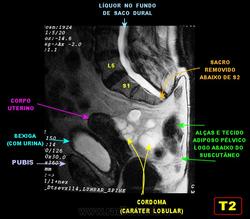

Сакральная хордома. Д-р Марсело Сенна Ксавье де Лима, Paul Roland Kaleff, и Антонио Рожерио del'Arco Roth Аугусто Варгас. Рецидив. Часть крестца была удалена ранее. Пнд, 27/11/2017 - 21:03 #1 Катенёв Валенти... Не на сайте Был на сайте: 7 лет 4 месяцев назад Зарегистрирован: 22.03.2008 - 22:15 Публикации: 54876 Внутричерепная хордома. http://pubs.rsna.org/doi/full/10.1148/rg.234025176 Пнд, 09/07/2018 - 20:44 #2 Катенёв Валенти... Не на сайте Был на сайте: 7 лет 4 месяцев назад Зарегистрирован: 22.03.2008 - 22:15 Публикации: 54876 Продолжение. Приложения: